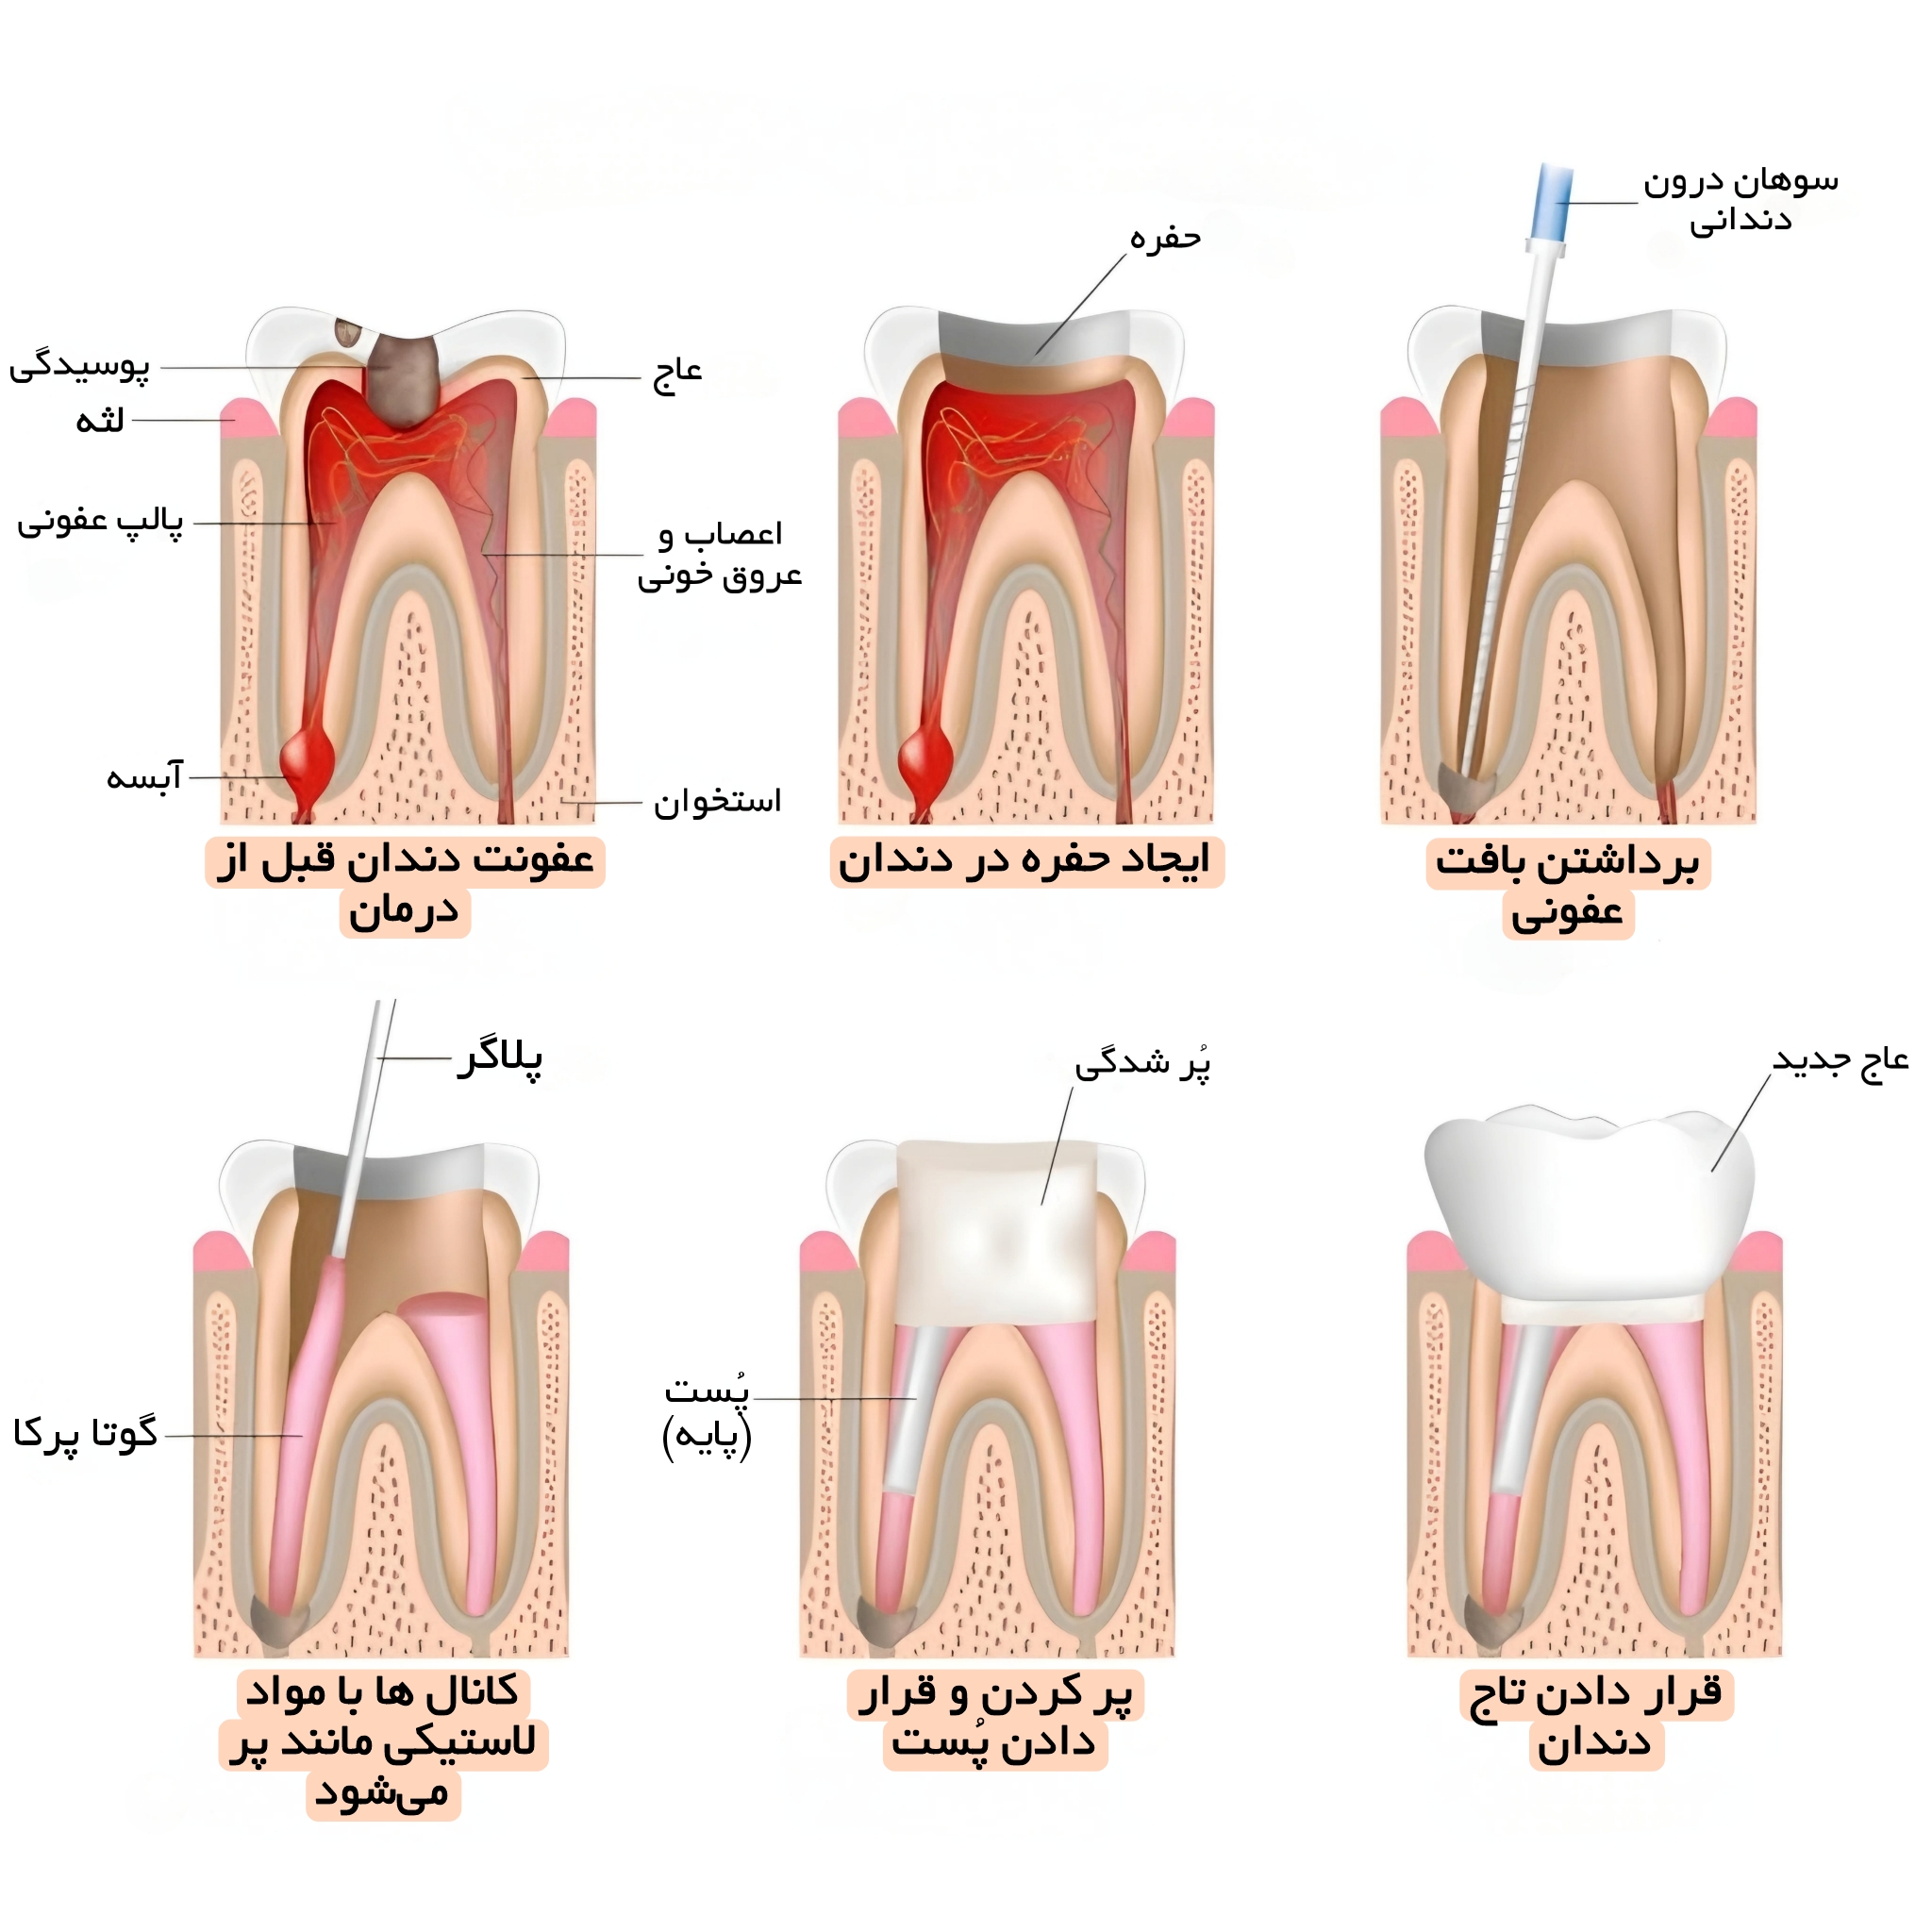

مراحل درمان ریشه دندان یا عصب کشی دندان

در مرحله اول ابتدا، برای انجام معاینه و بررسی وضعیت و میزان آسیب دندان عکس رادیولوژی (عکس opg )از دندان گرفته می شود. به منظور این که درد هنگام انجام درمان ریشه دندان فرد را اذیت نکند، از داروی بی حسی موضعی برای جلوگیری از احساس درد استفاده می شود. البته درد هنگام عصب کشی دندان ممکن است به خاطر آبسه و عفونت دندان بسیار زیاد باشد. بعد از بی حس کردن دندان، میله پلاستیکی برای خارج کردن بزاق دهان، داخل دهان بیمار قرار داده می شود.. سپس پوسیدگی هایی که در دندان ایجاد شده است، برداشته شده و عاج دندان برای دسترسی به ساقه پالپ دندان باز می شود. و از یک ابزار کوچک هم برای خارج کردن عفونت ها استفاده می شود.

در مرحله دوم عصب کشی دندان پس از برداشتن پالپ آسیب دیده، ساقه پالپ و کانال های ریشه خالی و تمیز می شوند. این مهم است که قبل از پر کردن دائم کانال های ریشه، تمامی بخش های کانال از تمام عفونت ها پاک شده و خشک شوند. البته این نکته را هم باید بگوییم که هنگام تمیز و خالی کردن کانال های دندان، کانال های ریشه دندان ممکن است تغییر شکل بدهند و بزرگ شوند تا به دسترسی برای پر کردن دندان راحت تر انجام شود. بعد از خالی کردن و تمیز کردن کانال دندان داروهایی به منظور تمیز کردن و خالی کردن دندان ار هرگونه عفونتی داخل کانال دندان ریخته می شود و ممکن است دندان بیمار برای خارج شدن مایع و ترشحات احتمالی از آن برای چند روز باز باقی بماند. اگر عفونت به لایه های داخلی دندان یعنی ریشه دندان نفوذ کرده باشد، ممکن است برای بیمار آنتی بیوتیک تجویز شود. چنانچه درمان ریشه دندان نیازمند چند جلسه درمان باشد، دندان را به صورت موقت پر می کنند تا دندان از مواد غذایی و تماس با بزاق دور نگه داشته شود. در هر صورت در این مدت از جویدن یا گاز گرفتن با استفاده از دندانی که در حال عصب کشی است تا زمانی که دندان درمان شده و ترمیم شود، پرهیز کنید.

پس از خالی کردن عفونت ها به صورت کامل و خشک کردن دندان، کانال دندان پر می شود. در این مرحله ممکن است نیاز به تزریق مواد بی حسی باشد. اگر همانطور که در مرحله دوم گفته شد دندان شما به صورت موقتی پر شده باشد، ابتدا این پر کردگی برداشته می شود تا به این ترتیب بتوان به ناحیه داخل دندان دسترسی پیدا کرد. در این مرحله از مواد مخصوص دندان پزشکی برای پر کردن دندان استفاده می شود تا به این ترتیب بتوان از حفاظت کانال های ریشه در برابر بزاق و نفوذ مواد خارجی اطمینان پیدا کرد.

همان مرحله ترمیم دندان می باشد. به دلیل اینکه دندان معمولاً در این حالت به دلیل پوسدگی زیاد صعیف شده است و به صورت زیاد پر شده است لازم است به منظور حفاظت از آن در برابر آسیب های آتی و نیز کمک به بازگشت دندان به عملکرد طبیعی آن ترمیم دندان انجام شود. انجام ترمیم دندان به وسیله روکش دندان صورت می گیرد که باعث می شود دندان طبیعی به نظر برسد. روکش دندان معمولا از جنس طلا، پرسلن یا ترکیبی از پرسلن و فلز ساخته می شود. روکش ساخته شده از پرسلن یا ترکیب پرسلن و فلز می تواند سایه زده شود تا به رنگ سفید دربیاید و تفاوتی با سایر دندان ها نداشته باشد.